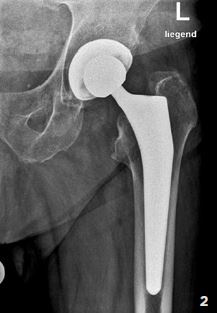

Operation

Abb. 2

Röntgenbild einer zementfreien Hüftprothese.

Die raue Beschichtung der Prothesen- Oberfläche

ermöglicht ein gutes Einwachsen in

den Knochen.